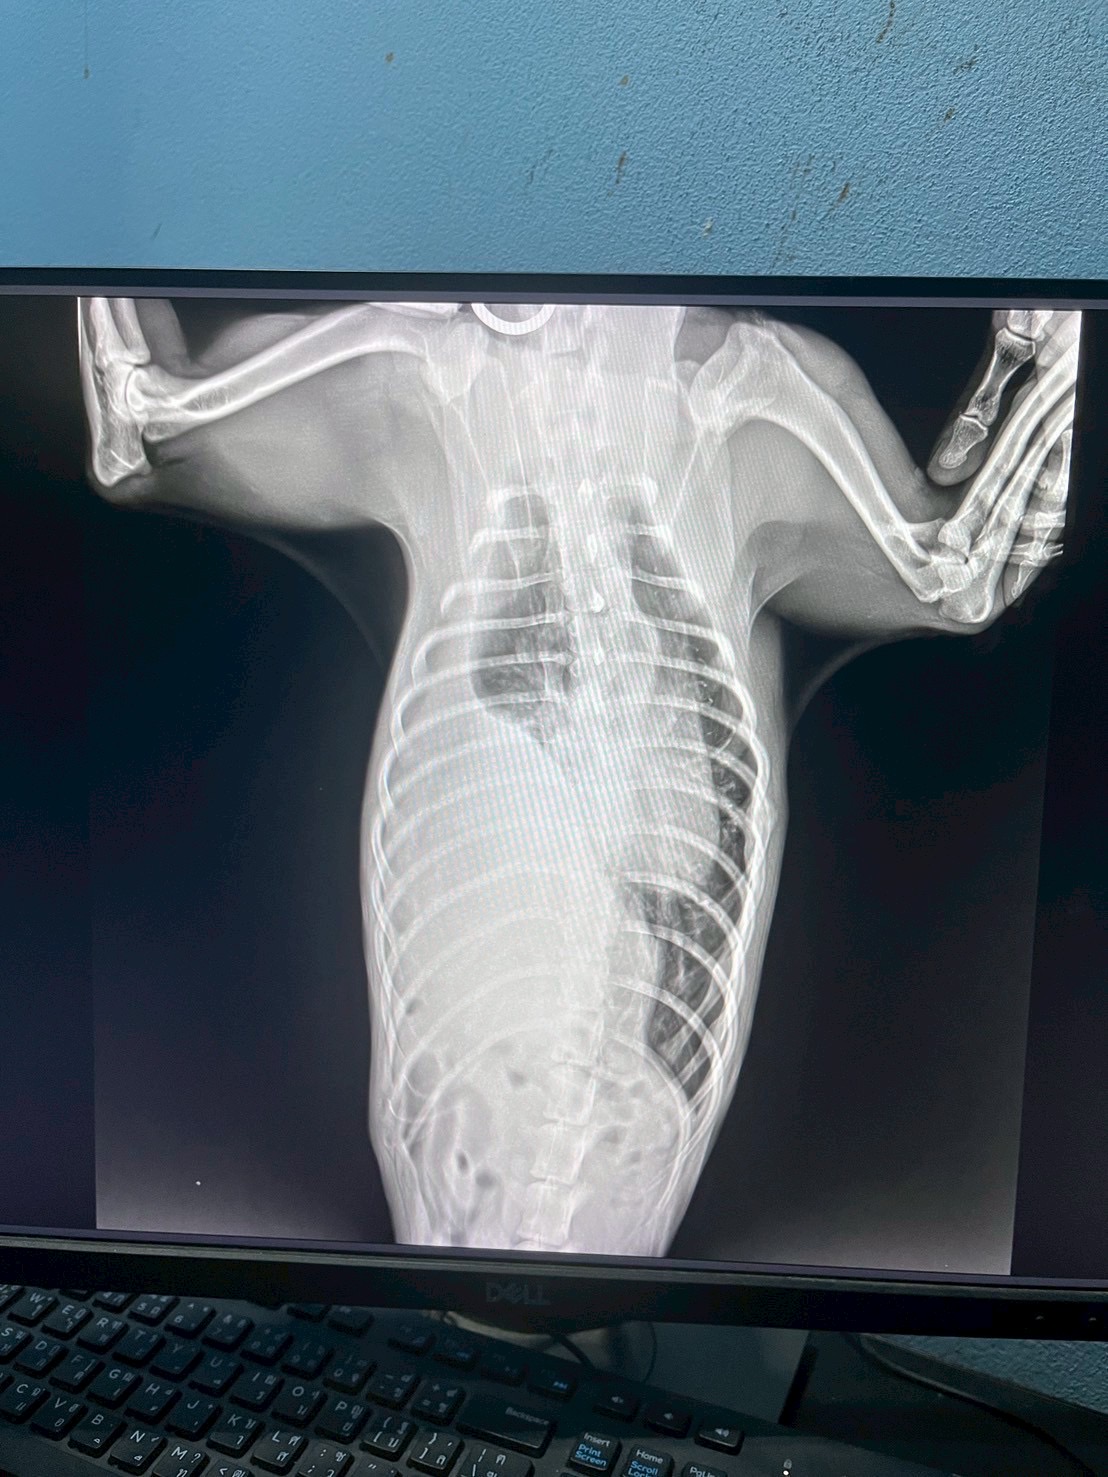

ทีมสัตวแพทย์ของเราได้รับเคสฉุกเฉินจากอุบัติเหตุที่ทำให้สัตว์เลี้ยงตัวหนึ่งได้รับบาดเจ็บรุนแรง กะบังลมฉีกขาดส่งผลให้อวัยวะในช่องท้องเคลื่อนเข้าไปในช่องอก ทำให้เกิดภาวะหายใจลำบาก หลังจากตรวจวินิจฉัยด้วยภาพรังสี ทีมสัตวแพทย์ได้ตัดสินใจเข้าผ่าตัดแก้ไขโดยการเย็บกะบังลม และจัดอวัยวะกลับสู่ตำแหน่งปกติ ผลลัพธ์เป็นที่น่าพอใจ น้องสามารถหายใจได้ตามปกติและกลับมาใช้ชีวิตได้อย่างมีความสุข โรงพยาบาลสัตว์ของเราพร้อมดูแลสัตว์เลี้ยงทุกตัวด้วยทีมแพทย์ผู้เชี่ยวชาญ หากพบอุบัติเหตุหรือภาวะฉุกเฉิน